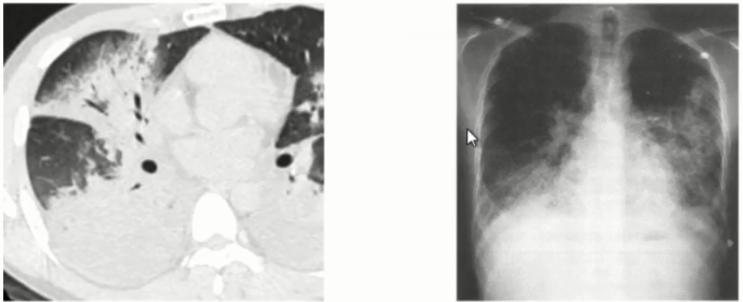

图6 患者在院外胸部影像学变化。左上肺小块实变,逐渐累积至右下肺,而且左上肺实变扩大和膨胀不全。

图8 患者入院当日胸部CT。左上肺大面积实变,右上肺斑片影,出现胸腔积液